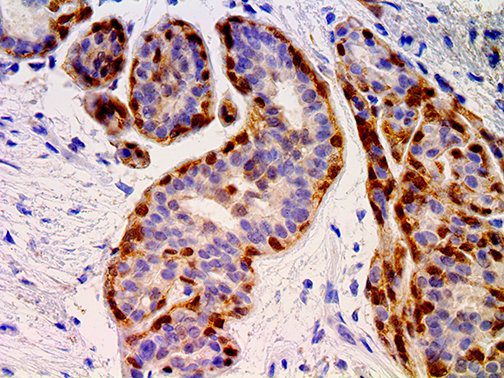

It is the ICU physician who is most likely to witness one of the deadliest manifestations of the abnormal immunological response, the cytokine storm syndrome (CSS). This response is also referred to by some as the cytokine release syndrome (CRS). CSS is characterized by continuous activation and expansion of macrophage and lymphocyte populations, which secrete large amounts of cytokines, causing the cytokine storm. This massive cytokine release is akin to hemophagocytic lymphohistiocytosis (HLH) disease, a syndrome characterized by initial unchecked and persistent activation of cytotoxic T lymphocytes and NK cells.

Clinical and laboratory manifestations of HLH include fever, enlarged liver and/or spleen, neurologic dysfunction, coagulopathy, liver dysfunction, cytopenias (i.e., low levels of erythrocytes, leukocytes, and/or platelets), hypertriglyceridemia, hyperferritinemia, hemophagocytosis, and eventually diminished NK cell activity as the immune system becomes progressively paralyzed. HLH can be familial (primary HLH) or secondary to another disease process (sHLH), such as rheumatic disease, in which it is referred to as macrophage activation syndrome (MAS, characterized by elevated ferritin).